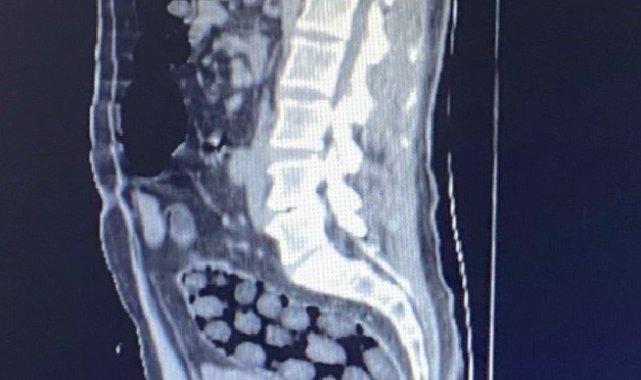

Bitlis'te mide ve bağırsaklarında toplam 91 paket uyuşturucu madde olduğu belirlenerek gözaltına alınan yabancı uyruklu 3 kişi, çıkarıldıkları adli mercilerce tutuklanarak cezaevine gönderildi.Bitlis Valiliğinden yapılan açıklamada, uyuşturucu ile mücadele kapsamında elde edilen istihbari bilgiler doğrultusunda Tatvan'da durdurulan bir otobüste yabancı uyruklu 3 yolcunun yakalandığı belirtildi. Açıklamada, "Bitlis Emniyet Müdürlüğü Narkotik Suçlarla Mücadele Şube Müdürlüğü ve İstihbarat Şube Müdürlüğü ekiplerince gözaltına alınan ve Tatvan Devlet Hastanesine sevk edilen şüphelilerin röntgen ve tomografi görüntülerinde mide ile bağırsaklarında çok sayıda yabancı cisim bulunduğu tespit edilmiş, yapılan tıbbi müdahale ile şüphelilerin paketleyerek yuttuğu toplam 91 adet daralı ağırlığı 1 kilo 126 gram metamfetamin maddesine el konulmuştur. Şüpheliler, çıkarıldığı adli mercilerce tutuklanarak cezaevine gönderilmiştir. Hemşehrilerimizin huzuru ve güvenliği için uyuşturucu madde imalatı, kaçakçılığı ve kullanımına karşı yürütülen kararlı mücadelemiz devam edecektir" denildi.

Bitlis'te mide ve bağırsaklarında toplam 91 paket uyuşturucu madde olduğu belirlenerek gözaltına alınan yabancı uyruklu 3 kişi, çıkarıldıkları adli mercilerce tutuklanarak cezaevine gönderildi.